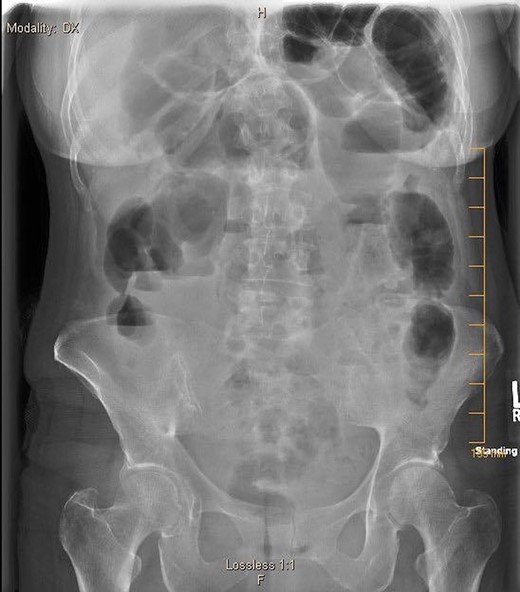

A 57-year-old non-toxic appearing female with a medical history of diverticulosis and malnutrition, and a surgical history significant for small bowel obstruction due to jejunal lymphangioma status post exploratory laparotomy and resection of bowel (2.2018). This patient presents with epigastric pain ×2 days with radiation to left upper quadrant and nausea with emesis, concerning for obstruction. In the Emergency Department, the patient was non-toxic appearing, hemodynamically stable, with no leukocytosis (7.4), or elevated lactic acid (1.2). Imaging, XR (Fig. 1) and CTAP (Fig. 2), demonstrating SBO with free air concern for perforated viscus. The concern for free air on imaging, in the setting of abdominal pain with symptoms of obstruction, mandated an operative intervention. On 7.5.18 the patient underwent exploratory laparotomy and was found to have emphysema of proximal jejunum, and underwent 125 cm resection of jejunum (Figs 3 and 4). Pathology of the specimen demonstrated multiple air filled cystic serosal nodules consistent with PCI (Figs 3 and 4, Supplementary Fig. S7).

7.4.18: XR abdomen acute complete w/chest: dilated small bowel loops in LUQ, air fluid levels in right mid abdomen, paucity of large bowel gas, suggestive of small bowel obstruction, suggestion of free air.